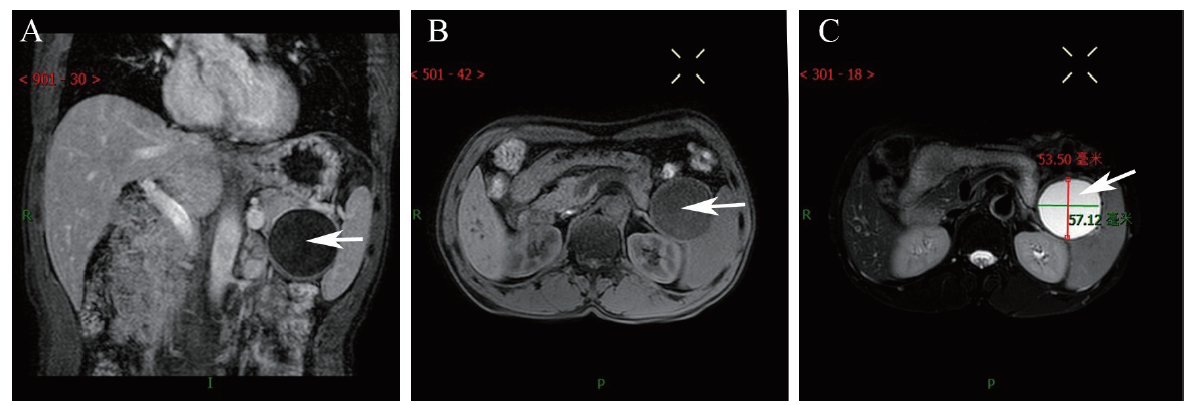

血常规、肝肾功能、血清淀粉酶、癌胚抗原、糖类抗原(CA)19-9、抗核抗体、抗中性粒细胞抗体、风湿因子、甲状腺功能和凝血功能未见异常。外院腹部CT:胰尾见类圆形低密度影,大小57.0 mm×65.0 mm,边界清,增强未见强化,考虑良性病变,假性囊肿可能性大(图1)。

图1 一例PLEC患者外院腹部CT图

注:A为CT平扫冠状位图片,胰尾见类圆形低密度影;B为CT平扫横断位图片;C为CT增强扫描横断位图片,低密度影未见强化;白色箭头所示为低密度影。